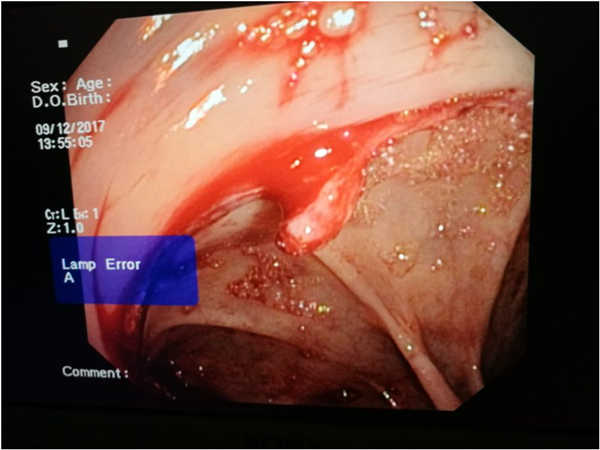

叮铃铃,一阵急促的电话声,扰乱了这个周末的清晨。“徐金锴,我们一个患者肠道出血,需要麻烦你过来,在肠镜下给看看,能不能止血”。徐金锴放下电话,用最快的速度,赶到医院,为患者进行治疗。因为这样的治疗,本身就有一定的难度,患者系肠道术后第一天,肠道吻合口还很脆弱,所以操作者需要有娴熟的技术和非常稳定的心理抗压力,再加上由于出血,肠道内全是积血,在胃镜下没有视野,需要耐心寻找出血点,动作要轻柔,要避免诱发其他并发症,再进行相应的止血等手段。时间滴滴答答在不经意间悄悄流逝,大家都已忘记了疲惫和辛苦,全神贯注的在注视着肠镜一点一点的接近病灶,经过漫长的寻找,在马双余老师的不断鼓励下,在赵耀、尚皓医生、陶静护士的通力配合下,通过大家不懈的努力,最终终于找到病灶,成功止血,挽救了患者的生命。喜悦之情溢于言表,每个人的脸上都洋溢着兴奋的喜悦!